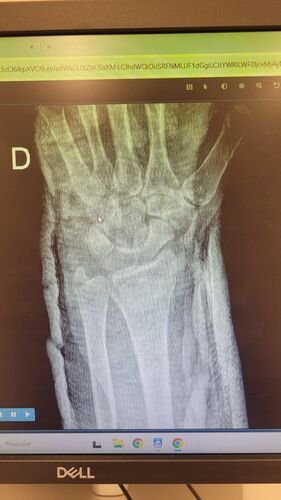

Meu nome e Isabella, mais conhecida como Snow, eu estava andando de muleta e a borracha dela saiu e eu tenho problema de equilibrio devido ao meu femur, bati o osso e piorou a situação, tive o radio do braço afetado e colocaram pino e deram um jeito de reverter porque eu ficaria com movimento do braço e mão comprometidos, tive traumatismo craniano porque bati a cabeça, esse ano eu já tinha sofrido um depois de um aparelho de raio x cair na testa mas fiquei sem sequelas na cabeça. Bom como muitos que me acompanham eu tenho uma condição rara entre mulheres que eu tenho os ossos do fêmur necrosados em mais de 75% desde 2022, eu sofri um acidente hoje andando de muleta, machuquei o fêmur, rosto, tivd que operar porque era uma emergência, não tenho muitas fotos pois estava internada mas tentei no SUS e não tinha pino de titânio,meu caso era de extrema urgência, eu to vendendo tudo e abrindo mão ate do meu apartamento pra cobrir a cirurgia e tenho ate final de setembro pra bater pelo menos 20 mil de meta, tenho inúmeras vakinhaa mostrando minha real doença autoimune e uma delas sendo rara que é osteonecrose bilateral do fêmur, o tratamento tá sendo todo particular mesmo sendo paciente do hospital das clínicas, ainda e difícil e nem sempre consigo as coisas, eu tento de todas formas é isso ainda pode me prejudicar na minha carreira, detesto pedir ajuda mas não tenho opção, a comunidade da minha área entre outros interesses sempre me apoiaram e infelizmente veio com humildade e de cabeça baixa pedir ajuda, faz tempo que tento recomeçar minha carreira desde o diagnóstico e nunca desisti dos meus sonhos e cirurgia

Vou deixar imagem atual do acidente abaixo e de algumas vakinhas anteriores